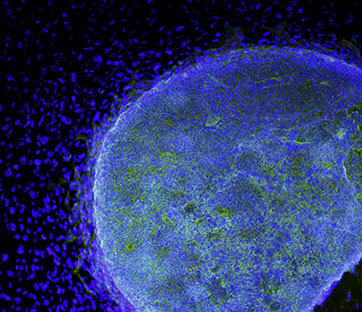

Per ora l’evidenza scientifica esiste solo sui topi di laboratorio ma i ricercatori inglesi sono fiduciosi. Per la prima volta il gruppo, guidato dal professor Robin Ali dell’University College of London, non è solo riuscito a far crescere in vitro dei fotorecettori degli occhi a partire da cellule staminali, ma li ha anche trapiantati con successo sul tessuto oculare di alcuni topi ciechi dove le stesse cellule si sono integrate completamente con la retina degli animali. Allo stato attuale non è ancora possibile dimostrare un qualsiasi miglioramento nella qualità visiva dei topi ciechi ma gli scienziati sono fiduciosi: esperimenti successivi saranno in grado di farlo e questo aprirà la strada per la sperimentazione sull’uomo, al massimo entro cinque anni, spiegano da Londra.

La perdita delle cellule fotosensibili dell’occhio, i coni e i bastoncelli, è la causa principale dell’insorgere di una serie di malattie degenerative tra cui la retinite pigmentosa, la degenerazione della macula (la parte più interna della retina) e la cecità legata al diabete. La ricerca sulle cellule staminali ha fatto passi in avanti notevoli nel riuscire a riprodurre svariati tipi di cellule adulte e di tessuti ma i progressi sulla retina si erano rilevati ben più difficili rispetto a esperimenti in altri ambiti. “La tecnica in 3D usata nella nostra ricerca - prosegue Ali - ci ha permesso di ricreare cellule al giusto stato di maturazione per poi essere trapiantate con successo. Il passo successivo sarà quello di migliorare questa tecnica usando cellule umane”.

I ricercatori, finanziati dal Medical Research Council, sono riusciti a trapiantare nella retina dei topi circa 200.000 cellule, interamente cresciute in vitro grazie all’uso delle staminali. Lo studio è stato pubblicato sulla rivista Nature biotechnology.